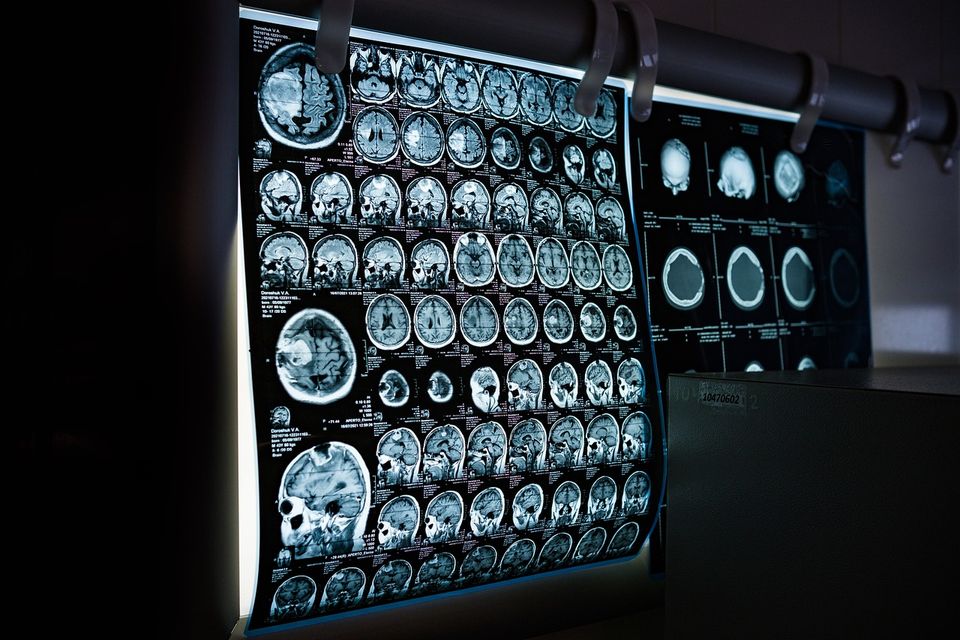

Lucy Brown, neurocercetător și profesor de neurologie, a condus un studiu pentru care au scanat creierele unor persoane îndrăgostite, cu ajutorul unui aparat cu rezonanță magnetică funcțională (fMRI).

Analiza a vizat 10 femei și șapte bărbați care erau intens „îndrăgostiți”, pe baza scorurilor lor pe scara iubirii pasionale, un chestionar cu 14 elemente conceput pentru a evalua aspectele cognitive, emoționale și comportamentale ale iubirii pasionale, pe care cercetătorii din domeniul relațiilor l-au folosit pe scară largă timp de decenii.

Participanții la studiul lui Brown au privit alternativ o fotografie a iubitei lor și o fotografie a unei persoane familiare. Atunci când au privit fotografia partenerului lor romantic, participanții au experimentat o activare cerebrală în zona tegmentală ventrală (VTA) a creierului mijlociu, care este partea creierului legată de satisfacerea nevoilor de bază, cum ar fi să bem

atunci când ne este sete și să mâncăm atunci când ne este foame.

Un alt studiu, coordonat de Stephanie Cacioppo, doctor în neuroștiințe, a descoperit că 12 zone ale creierului colaborează pentru a elibera substanțe chimice precum dopamina, hormonul „stării de bine”, oxitocina, hormonul „îmbrățișării”, și adrenalina, care induce un sentiment euforic de scop. Descoperirile sale au indicat, de asemenea, că circuitul de recompensă al creierului- amigdala, hipocampul și cortexul prefrontal- care este foarte sensibil la comportamentele care induc plăcere, se aprinde pe scanările cerebrale atunci când se vorbește despre o persoană dragă, din cauza creșterii fluxului sanguin în aceste zone.